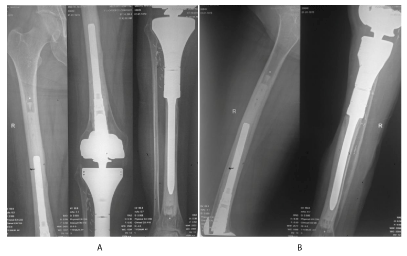

A 33 year - old female patient presented for right leg pain of a five week duration, exacerbated by weight bearing without disappearing at rest or at night. She estimates the pain as 6 over 10, relieved with non-steroidal anti - inflammatory agents. She is previously healthy without any history of trauma. There is mild edema, no redness, and mild increase of the pain upon palpation. There are no neurovascular abnormalities. Examination of the back, hip, and knee is normal. X-ray showed a large hypolucent spherical lesion in the proximal third of the tibia (Figure 1). MRI on T1 showed the lesion to be hypointense, and on T2 to be hyperintense (Figure 2,3). The lesion showed to be osteolytic, extending anteroposteriorly through the cortex at some levels, but it did not reach the articular surface, nor the surrounding soft tissues. Decision was taken to biopsy it. The pathology report showed lamellated cysts and scattered scoleces. Albendazole 400 mg was given orally twice per day for 2 months. Extensive curettage was done through excision of bone layers with a burr, then phenolization and grafting of cancellous bone chips inside the cavity. The patient was free clinically and radiologically of the disease for two years, then in the third year, multilocular cysts reappeared on x-ray (Figure 4), with possible extension to the articular surface. A decision of total knee arthroplasty was taken after wide resection of the diseased segment (Figure 5). Negative margins were obtained. The patient post operatively was rehabilitated; pain subsided with no radiological signs of recurrence. She was given albendazole 400 mg orally twice per day for 3 months.